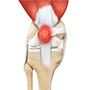

Ligaments of the Knee

Ligaments are tough bands of tissue that connect one bone to another bone. The ligaments of the knee function to stabilize the knee joint. There are two important groups of ligaments that hold the bones of the knee joint together, collateral ligaments and the cruciate ligament.

Collateral ligaments are present on either side of the knee. They function to prevent the knee from moving too far during side to side motion. The collateral ligament on the inside is called the medial collateral ligament (MCL) and the collateral ligament on the outside is called the lateral collateral ligament (LCL).

Cruciate ligaments, present inside the knee joint, control the back-and-forth motion of the knee. The cruciate ligament in the front of the knee is called anterior cruciate ligament or ACL and the cruciate ligament in the back of the knee is called posterior cruciate ligament or PCL.